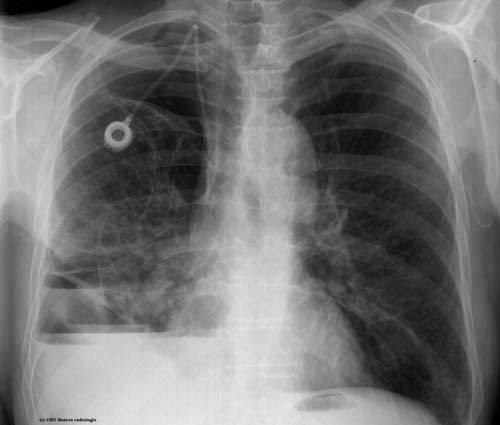

Pneumothorax